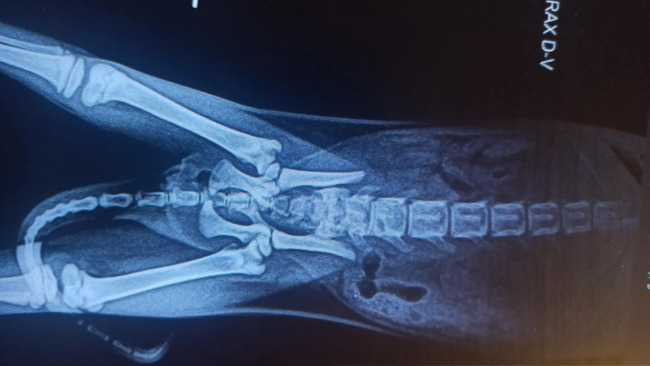

Kolejny połamany maluch 😭 Bejbik – uroczy, ufny. Uszkodzenie miednicy wskazuje na to że ktoś go kopnął ☹ A on … nadal tuli się, kocha, ufa

Potrzebuje RTG, konsultacji ortopedycznej, leków, szczepionek. Pomożecie go uratować?